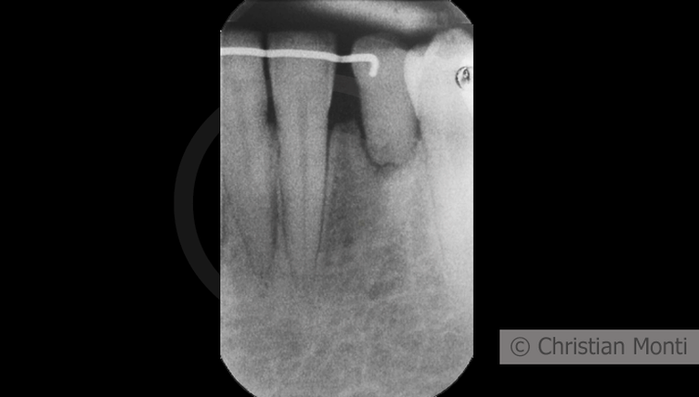

EDENTULIA SINGOLA

Impianto in sostituzione di un canino deciduo